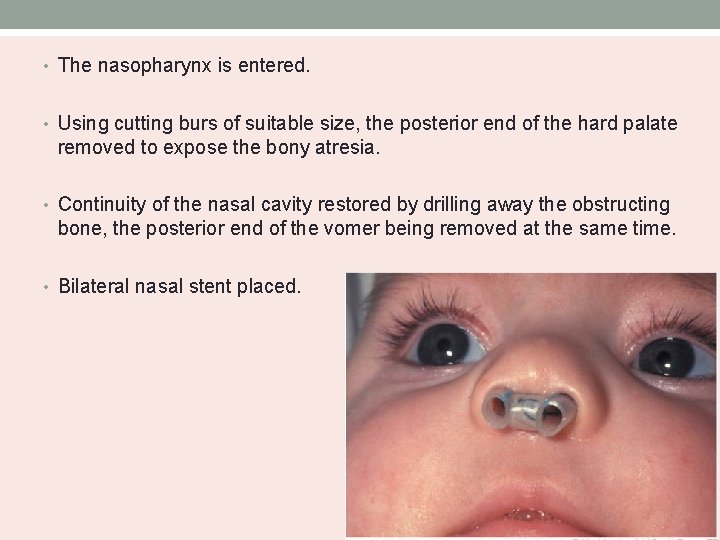

• The nasopharynx is entered. • Using cutting burs of suitable size, the posterior end of the hard palate removed to expose the bony atresia. • Continuity of the nasal cavity restored by drilling away the obstructing bone, the posterior end of the vomer being removed at the same time. • Bilateral nasal stent placed.